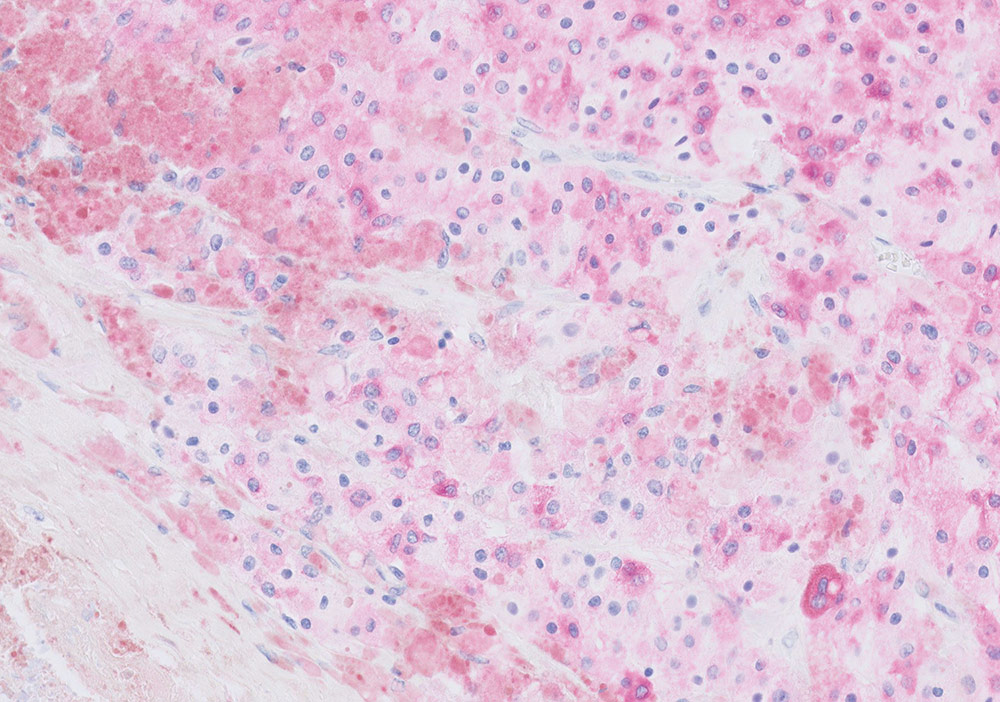

When diagnosing cancer, pathologists typically stain tumor samples with a brown stain called DAB. However, for skin and lung biopsies, they usually choose a red stain as it contrasts well with the brown melanin color in skin, and any pollution artifacts that are typical in lung tissue.

HRP Magenta has a transparent nature, yet is clearly visible, distinct and intense. This allows the pathologist to recognize tissue structures and cellular details even in strongly stained cases. Nuclei can be easily identified, and all details are visible.

HRP Magenta is designed for use on Dako Omnis, the company's flagship instrument for immunohistochemistry and in situ hybridization. Derived from a well-known chromogen used for many years in other industries, the molecule has been modified for use in cancer diagnostics.